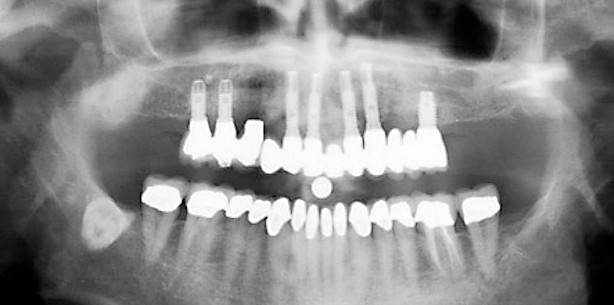

3. die Zonenverteilung im Oberkiefer, wie sie sich in einem OPG darstellt.

Um festzustellen, ob axiale Implantate, geneigte Implantate oder das Zygoma-Implantatkonzept geeignet sein können, wird der Alveolarkamm in drei separate Zonen eingeteilt:

- Zone 1: von Eckzahn zu Eckzahn

- Zone 2: der Prämolarenbereich

- Zone 3: der Molarenbereich

Das Vorliegen oder der Mangel an ausreichendem Knochen in den verschiedenen Zonen hat einen großen Einfluss auf die Wahl der chirurgischen Technik (Tab. 1).

Ist der Knochen in allen drei Zonen angemessen, können axiale Implantate eingesetzt werden (Abb. 8). Das geneigte Implantatkonzept sollte in Betracht gezogen werden, wenn die Zonen I und II ausreichend Knochen aufweisen (Abb. 9). Ist nur in Zone I ausreichend Knochen vorhanden, sollte das Zygoma-Behandlungskonzept in Betracht gezogen werden (Abb. 10). In den seltenen Fällen, in denen es in allen drei Zonen an ausreichendem Knochen fehlt, sollte das Konzept Quad Zygoma in Erwägung gezogen werden (Abb. 11). 3